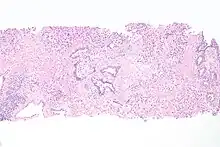

Transitional cell carcinoma, being low-grade to the left, and high-grade to the right. H&E stain

Papillary transitional cell carcinoma, low grade

Histopathology of urothelial carcinoma of the urinary bladder, showing a nested pattern of invasion. Transurethral biopsy. H&E stain

Histopathology of urothelial carcinoma of the urinary bladder.